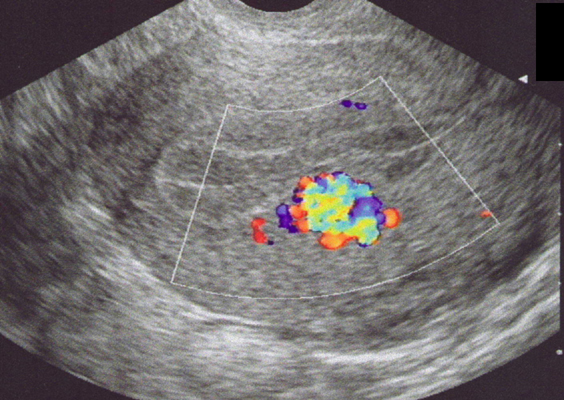

Fistule artério-veineuse au sein de l’endomètre après curetage (Doppler couleur) (Cliché : Dr. C. TALMANT)